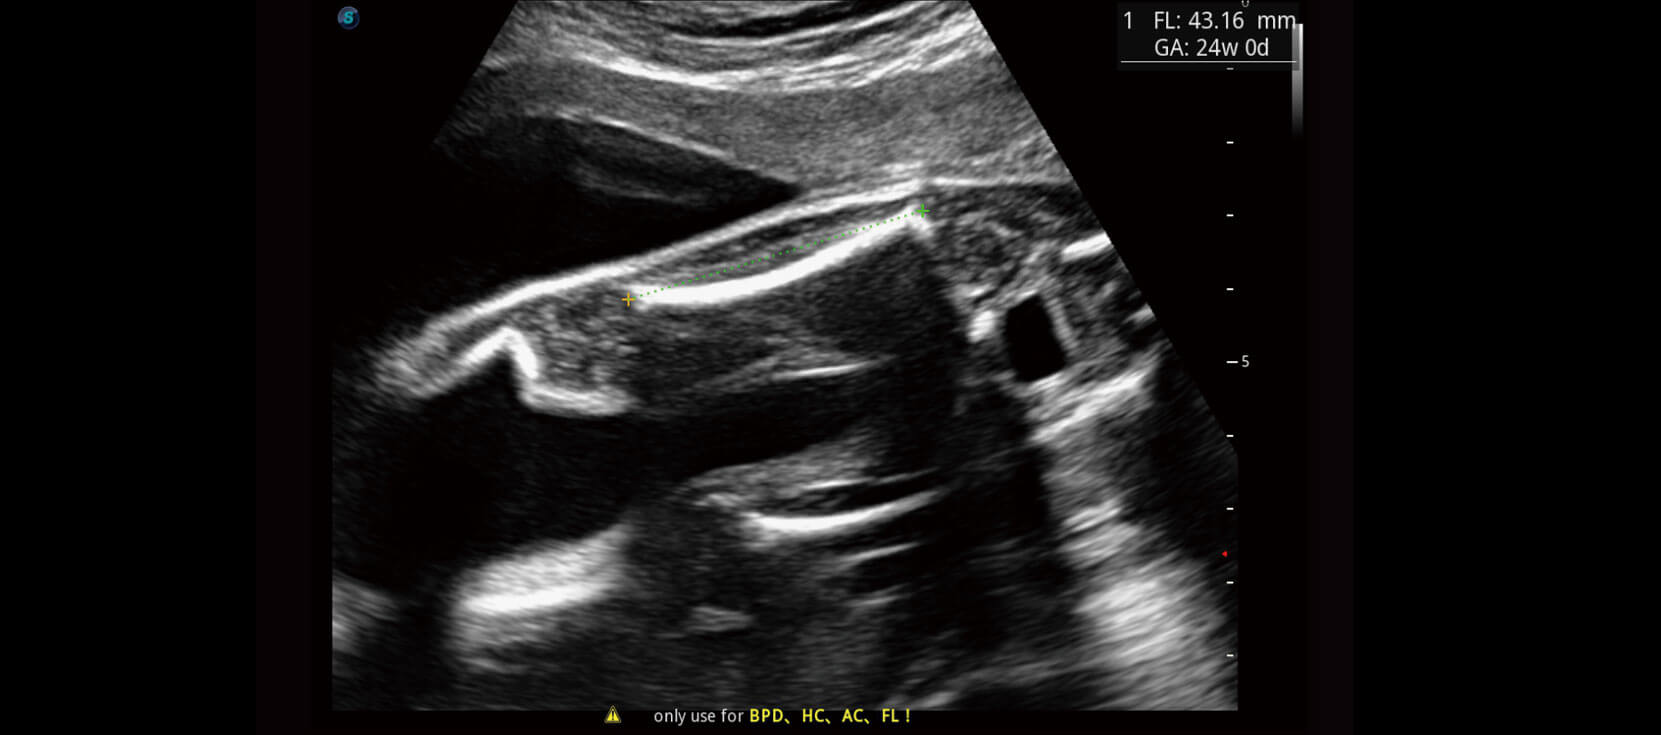

Tự động phát hiện và đo 16 thông số thai nhi bằng trí tuệ nhân tạo AI trong quy trình siêu âm sản khoa.

Tự động thu thập mặt phẳng tiêu chuẩn (có sẵn trên BPD/AC/HC/FL).

Sinh trắc học và báo cáo tự động.

Đã xác minh hơn 10000 trường hợp với độ chính xác 98%.

Auto OB

Tự động OB giúp siêu âm thai nhi nhanh chóng và hiệu quả. Kết quả nhất quán làm giảm sự thay đổi phụ thuộc vào người dùng.